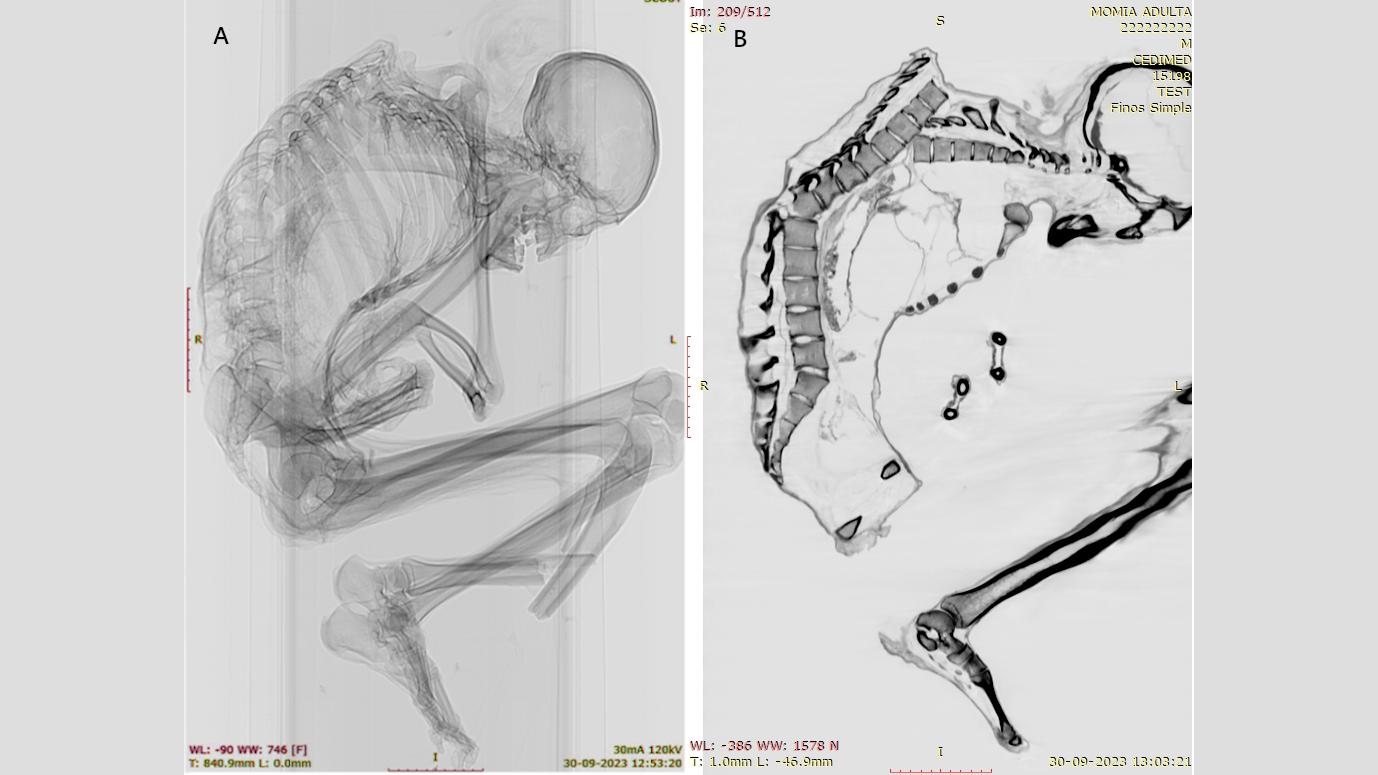

Multiple unhealed fractures were evident on the man’s upper spine. He also had rib, shoulder blade and collarbone fractures, which suggest “a blunt force impact over a wide area” of his upper back, revealing his “upper left thorax bore the brunt of the impact,” Morales and Garrido wrote in the study. The impact displaced several of his vertebrae and collapsed his rib cage.

Additionally, the researchers identified a fracture in a vertebra near the base of his spine, likely the result of the initial upper-back injury. The upper- and lower-spine injuries are both “typically associated with severe spinal cord damage and high mortality,” the researchers wrote.

But there were no injuries found to the man’s skull, neck or arms, which indicates that the impact occurred when the man was in a head-down body position. He may have been actively mining or perhaps attempting to protect his head with his arms when he was struck by a heavy object falling from above. This type of injury is seen in the bodies of people involved in earthquakes and in occupational accidents in forestry, construction and mining, the researchers wrote.